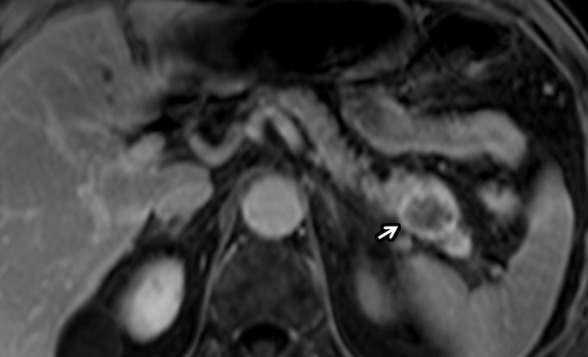

Figure 11a:

Pancreatic adenocarcinoma in a 67-year-old man with Li-Fraumeni syndrome (TP53 mutations) with prior history of lung and prostate cancers. (a) Axial postcontrast T1-weighted and (b) diffusion-weighted images show incidentally detected hypovascular mass (arrow) in the pancreatic tail with restricted diffusion during screening MRI. This was proven to be PDAC following distal pancreatectomy.

Figure 11b: